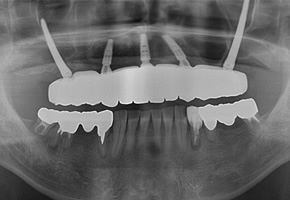

CASE01:All on 4

下の歯は4本、上の歯は5本インプラントを埋め込み、上下ともに1日で歯をセットしました。上の歯に関しては、単に5本埋入すればいいという問題ではありません。

| コメント | 「歯がボロボロで、このままでは何も噛めない」とお悩みの高齢70代のの女性の患者さんが、東京都内でインプラント治療を探されて当院に来院されました。 長年のむし歯と歯周病により、上も下もご自身の歯ではほとんど噛めない状態で、「入れ歯は合わないのですぐにしっかり噛みたい」というのが一番のご希望でした。当院ではまずCTによる精密検査を行い、骨量が大きく失われていた上顎には通常のインプラントではなく、頬骨を利用するザイゴマインプラントを選択しました。 下顎には4本のインプラントで全体の歯を支える「オールオン4(All-on-4)インプラント」を計画し、噛み合わせや負担のバランスを綿密に設計したうえで手術に臨みました。「手術が怖い」「痛みが心配」という不安をお持ちだったため、点滴でお薬を入れてうとうとリラックスした状態で治療が受けられる「静脈内鎮静法」を併用しました。 全身麻酔とは異なり意識は保ちながらも、手術中の恐怖心や痛みの記憶がほとんど残らず、長時間のインプラント手術でも安心して受けていただける方法です。手術当日に上顎ザイゴマインプラントと下顎オールオン4のインプラントを埋入し、十分な初期固定が得られたため、その日のうちに固定式の仮歯を装着しました。 「久しぶりに自分の歯で噛めているような感覚」「手術の記憶もあまりなく、あっという間に終わった」と、柔らかいものから少しずつお食事を楽しんでいただけるようになりました。ザイゴマインプラントやオールオン4は、総入れ歯や「歯がボロボロ」でお困りの方、骨が少なく他院でインプラントが難しいと言われた方でも、しっかり噛める状態を目指せる高度なインプラント治療です。 当院ではインプラント専門の歯科医師が、静脈内鎮静法を用いた負担の少ない手術と、長期的なメインテナンスまで見据えた治療計画で、東京都エリアの患者さんの「すぐに噛みたい」という願いにお応えしています。 |